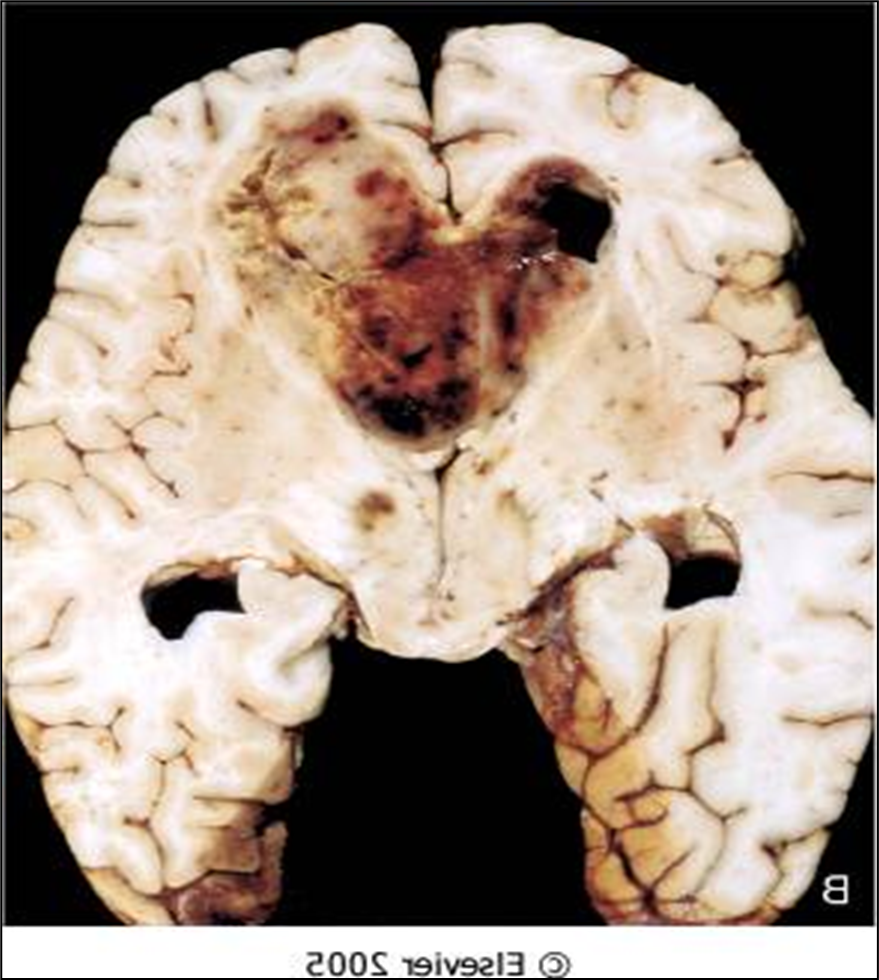

Lots of hemorrhaging, weak blood vessels, and necrosis growing fast

GBM

pleomorphic astrocytes

mitotic activity

vascular proliferation here

necrosis

know this picture!

Palisading neoplastic cells surrounding necrosis

GBM grade 4 astrocytoma

Geographic pattern, a perimeter of neoplastic glial cells surrounding necrosis